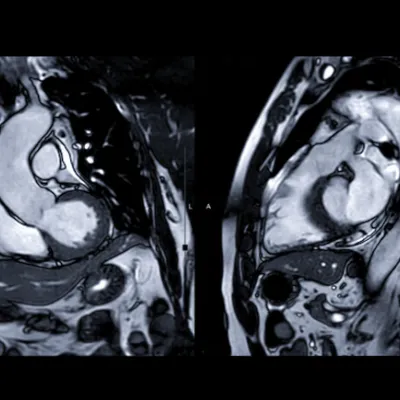

A cardiac magnetic resonance image (MRI), sometimes abbreviated as CMR, is a non-invasive imaging test that uses magnetic fields and radio waves to create images of the heart.